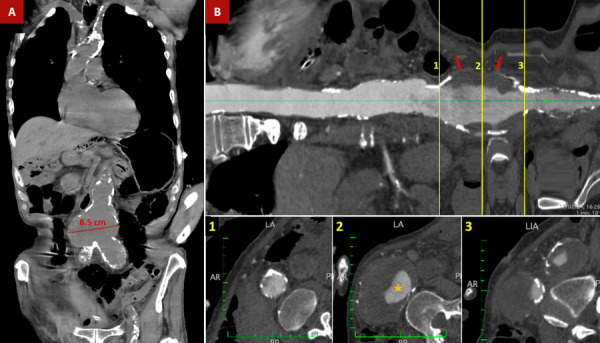

主动脉畸形(SA)的特征是胸腹主动脉发生严重而广泛的粥样病变。这种退行性危险病变是多种可改变和不可改变的危险因素共同作用的结果。这种病症的临床重要性在于其病因机制可能导致的各种综合征,从而给患者带来极大的发病率和死亡率。在本文件中,我们将对这一病症进行最新的详细综述,从病理生理学、诊断(包括多模态成像的重要性)和治疗方法等方面进行阐述。最后,我们介绍了 SA 患者在不同主动脉情况(主动脉夹层、溃疡斑块和血栓性动脉瘤)下的临床表现,从而说明了这种疾病的性质及其高死亡率。

Shaggy aorta (SA) is characterized by a critical and extensive atheromatous disease of the thoracic and abdominal aorta. This degenerative and dangerous pathology is the result of the confluence of multiple modifiable and non-modifiable risk factors. The clinical importance of this pathology relies on the various syndromes that can develop from its etiopathogenesis, which generates great morbidity and mortality in the affected patients. In this document, we present an updated and detailed review of this entity, developing aspects of its pathophysiology, diagnosis, including the importance of multimodal imaging, and its therapeutic approach. Finally, we present the clinical settings of patients with SA in different aortic scenarios (aortic dissection, ulcerated plaques, and thrombosed aneurysms) that denote the nature of this disease and its high mortality.